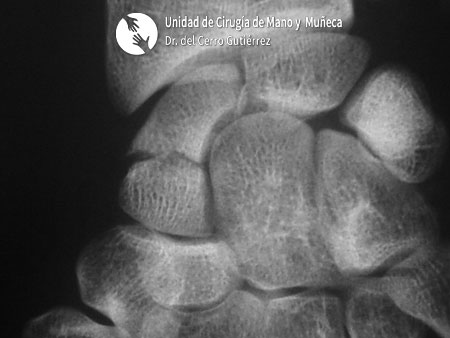

El escafoides es uno de los 8 huesos del carpo. Más de la mitad del escafoides está recubierto de cartílago articular, con una vascularización precaria a través de la rama carpiana dorsal, dependiente de la arteria radial.

La fractura del escafoides es una lesión en uno de los huesos pequeños del carpo llamado escafoides, ubicado en la base del pulgar, entre el radio y los demás huesos del carpo.

Su ubicación estratégica lo hace crucial para la estabilidad de la muñeca.